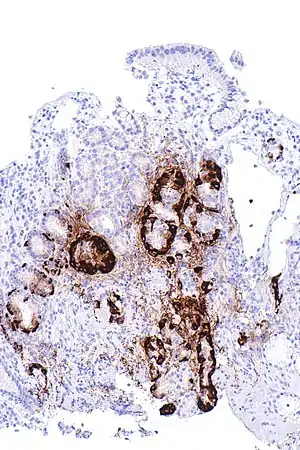

| Micrograph showing nodular enterochromaffin-like cell hyperplasia, as demonstrated with chromogranin A immunostaining, in the body of the stomach. Parietal cells are not readily apparent. These changes are in keeping with autoimmune metaplastic atrophic gastritis, a histologic correlate of vitamin B12 deficiency anemia. | |

PA may be considered as an end stage of autoimmune atrophic gastritis, a disease characterised by stomach atrophy and the presence of antibodies to parietal cells and intrinsic factor.[36][37] Autoimmune atrophic gastritis, is localised to the body of the stomach, where parietal cells are located.[34] Antibodies to intrinsic factor and parietal cells cause the destruction of the oxyntic gastric mucosa, in which the parietal cells are located, leading to the subsequent loss of intrinsic factor synthesis. Without intrinsic factor, the ileum can no longer absorb the B12.[38] Atrophic gastritis is often a precursor to gastric cancer.[37]